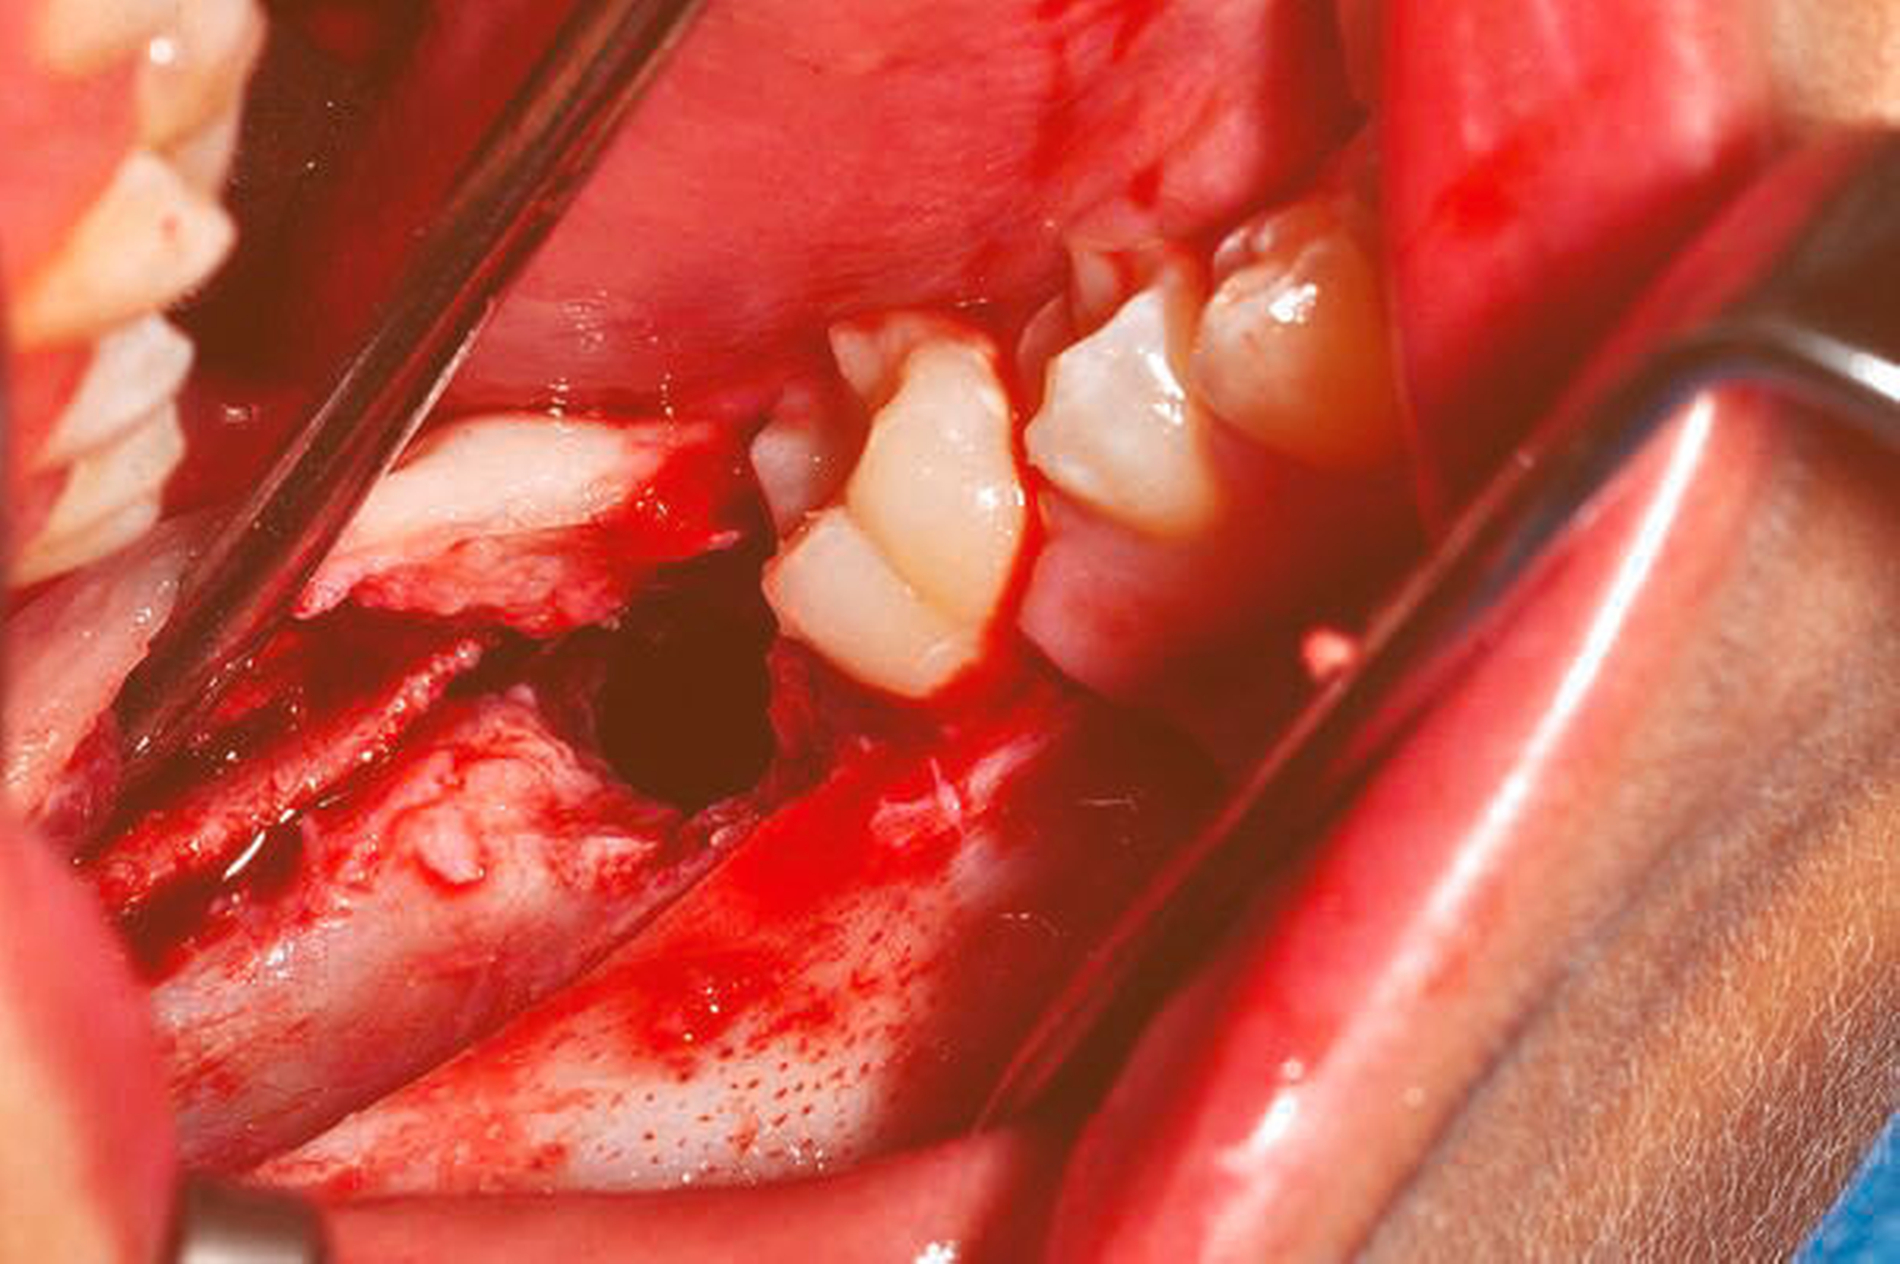

Unter der Verdachtsdiagnose einer follikulären Zyste wurde der Patient der operativen Therapie unter Intubationsnarkose zugeführt. Nach marginaler Schnittführung und distaler Entlastung entlang des aufsteigenden Astes des rechten Unterkiefers erfolgte die Anlage eines Knochendeckels mittels Piezochirurgie (Abbildung 3). Die Zyste wurde zusammen mit den retinierten Zähnen in toto exstirpiert (Abbildung 4) und zur histopathologischen Diagnostik versandt. Der Nervus alveolaris inferior am Boden der entstandenen Kavität (Abbildung 5) wurde vorher vorsichtig vom Zystenbalg entfernt. Anschließend wurde der Defekt mit Kollagen und autologem Knochen aufgefüllt. In der histopathologischen Aufbereitung zeigte sich ein durch flaches, mehrschichtiges Epithel ausgekleidetes fibrotisches Bindegewebe. Die Zystenwandung war fokal verdickt sowie äußerst zellreich mit monomorphen, unreif wirkenden Zellkernen. Die immunhistochemischen Analysen beschrieben eine zytoplasmatisch positive Färbereaktion auf CK-MNF und CK-Oscar. Der Proliferationsindex mit Ki-67 wies zwei bis fünf Prozent nukleär positive Zellen auf. Bei Chromogranin, S100 und Synaptophysin fand keine positive Färbereaktion statt. Somit konnte die Diagnose eines adenomatoiden odontogenen Tumors getroffen werden. Bei postoperativ komplikationslosem Heilungsverlauf konnte der Patient nach einem dreitägigen stationären Aufenthalt in die ambulante Weiterbetreuung entlassen werden. Zur weiteren Verlaufskontrolle wurde ein halbjährliches Nachuntersuchungsintervall vereinbart.